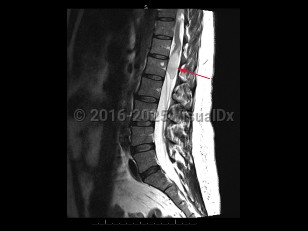

Cauda equina syndrome

Cauda equina syndrome is a neurologic emergency where damage to the lumbosacral plexus leads to loss of lower motor neuron function. Trauma, tumors or abscesses, large lumbar disk herniation, and spinal stenosis are some of the etiologies of this condition.

Onset is typically gradual but can be acute. Signs and symptoms include severe back pain that may radiate into one or both legs, saddle anesthesia, leg weakness or paraplegia, urinary or bowel dysfunction, sexual dysfunction, and gait disturbance. There may be reduced or absent patellar, Achilles, anal, and bulbocavernosus reflexes.

Prognosis depends on severity and duration of compression or damage to the affected nerves.